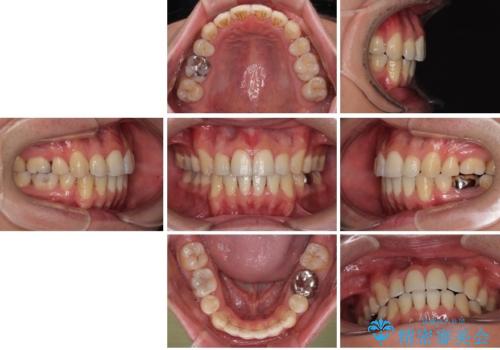

- 口元の突出感が強く、口が閉じにくいことを主訴として来院された患者さんの症例をご紹介します。

前歯部の叢生(デコボコ)も認められ、歯がきれいに並ぶためのスペースが不足している状態でした。

これらの問題を総合的に改善するため、上下左右の第一小臼歯を計4本抜歯し、スペースを確保する治療計画を立てました。

抜歯したスペースを活用して前歯を後ろへ下げることで、口元の突出感を大きく改善。

奥歯の噛み合わせがずれている「シザーズバイト」を適正に整えることで、見た目だけでなく機能性も向上し、安定した咬合が獲得できました。

口元の突出が改善され、横顔の印象が大きく変化し、口が自然に閉じやすくなりました

前歯のデコボコが整い、清掃性が向上

噛み合わせが改善し、長期的に安定する噛み合わせに

「見た目」と「機能性」の両方を改善できた、非常に満足度の高い治療となりました。